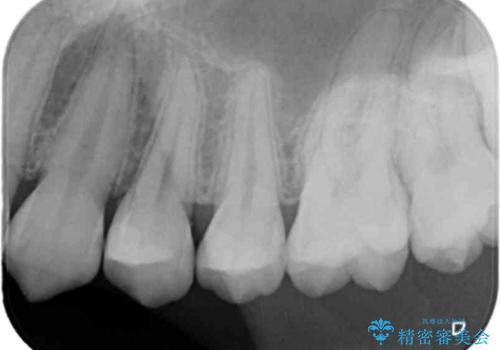

- 検査の結果、歯と歯の間に大きな虫歯が確認されました。

セラミックでの治療をご希望されたため、セラミックインレーでの治療を行いました。

今回は残せる歯の厚みが十分確保できたため、インレーでの修復処置となりました。